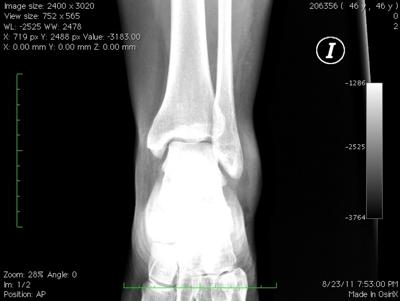

Whilst I look at lots of X-rays I'm not a trained radiologist, and thus I'm reluctant to give an opinion, particularly seeing that I can't examine your foot itself.

It does seem there is some swelling adjacent to the lateral malleolus, but I can't see any fracture. This is probably due to some sprain of the ligaments.

The posterior process of the talus seems somewhat enlarged, but has nothing to do with the injury. However, it would limit movement in the subtalar joint.